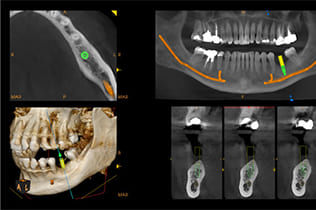

CTとインプラント治療

見えない顎の骨を可視化

インプラント治療の成功には、顎の骨の状態を正確に把握することが不可欠です。CTスキャンは、従来の2次元レントゲンでは得られない骨の量、質、厚み、そして神経や血管の正確な走行位置を3次元で立体的に把握できます。これにより、インプラントを埋入する最適な位置や角度を決定し、より安全で成功率の高い治療計画を立案することが可能です。偶発的な神経損傷などのリスクを最小限に抑え、患者様に安心して治療を受けていただけます。